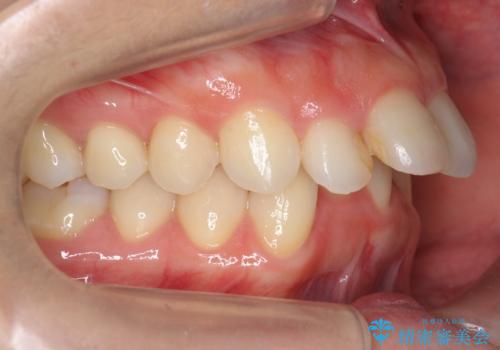

前歯がでている 最小限の抜歯で口を閉じやすく

- 出っ歯を主訴に来院。

上下のかみ合わせが1本分左右ともずれていました。

①上下左右合計4本抜歯(口元は一番下がるプラン、上の奥歯をさらに後ろに下げる必要があるため②より時間がかかる、上下正中は合う)

②上の歯を2本抜歯、下の歯は前歯1本と最小限の抜歯(矯正治療は早く終わる、口元は下がる、抜歯は3本、上下の正中は合わない)

を提示し、

②を選択されました。

下顎がとても小さく後方位であるため、オトガイの閉口時のシワは完全になくすことは難しかったですが、前歯も大きく下がり満足していただきました。

矯正治療は審美的な側面を持っておりますが、小さすぎる下の顎に口元を無理やりあわせるのも、歯の移動量が大きすぎて適切な治療とは言えないと思います。健康を損なう美容整形とは違うからです。前歯については、適度に下げる量をコントロールすることも大事です。